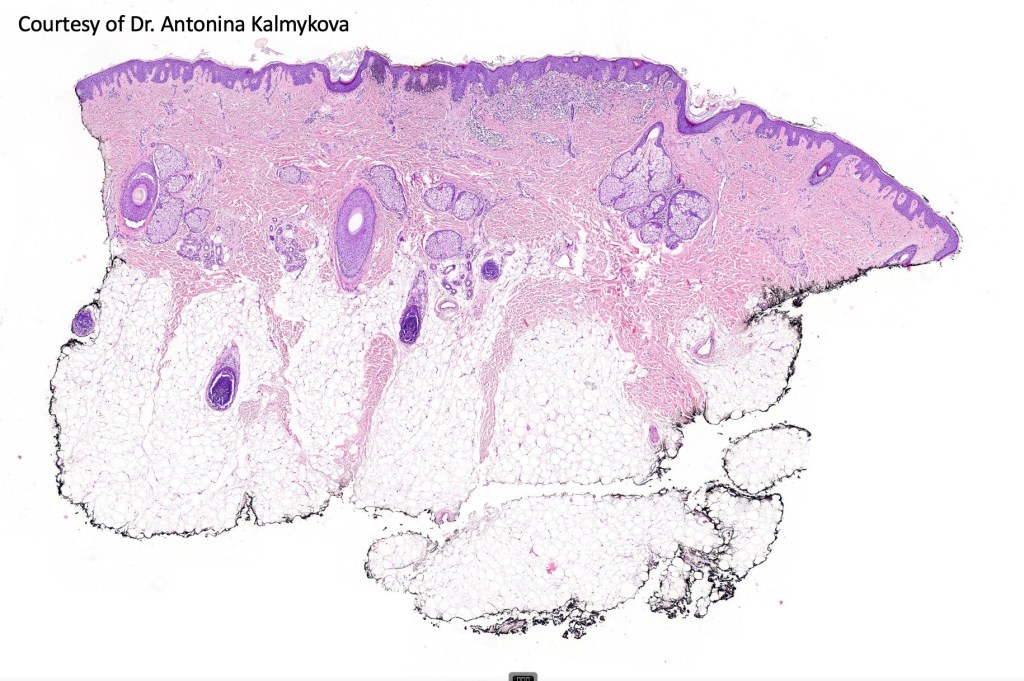

Although most scalp nevi can be readily classified into the regular nevus subtypes- common, congenital, blue etc, exceptionally they may show features more commonly seen at “the socalled milk-line” sites. Some authors use the term “atypical nevus of the scalp”.

Histological features

•Junctional/compound

•Dermal fibrosis (sometimes lamellar)